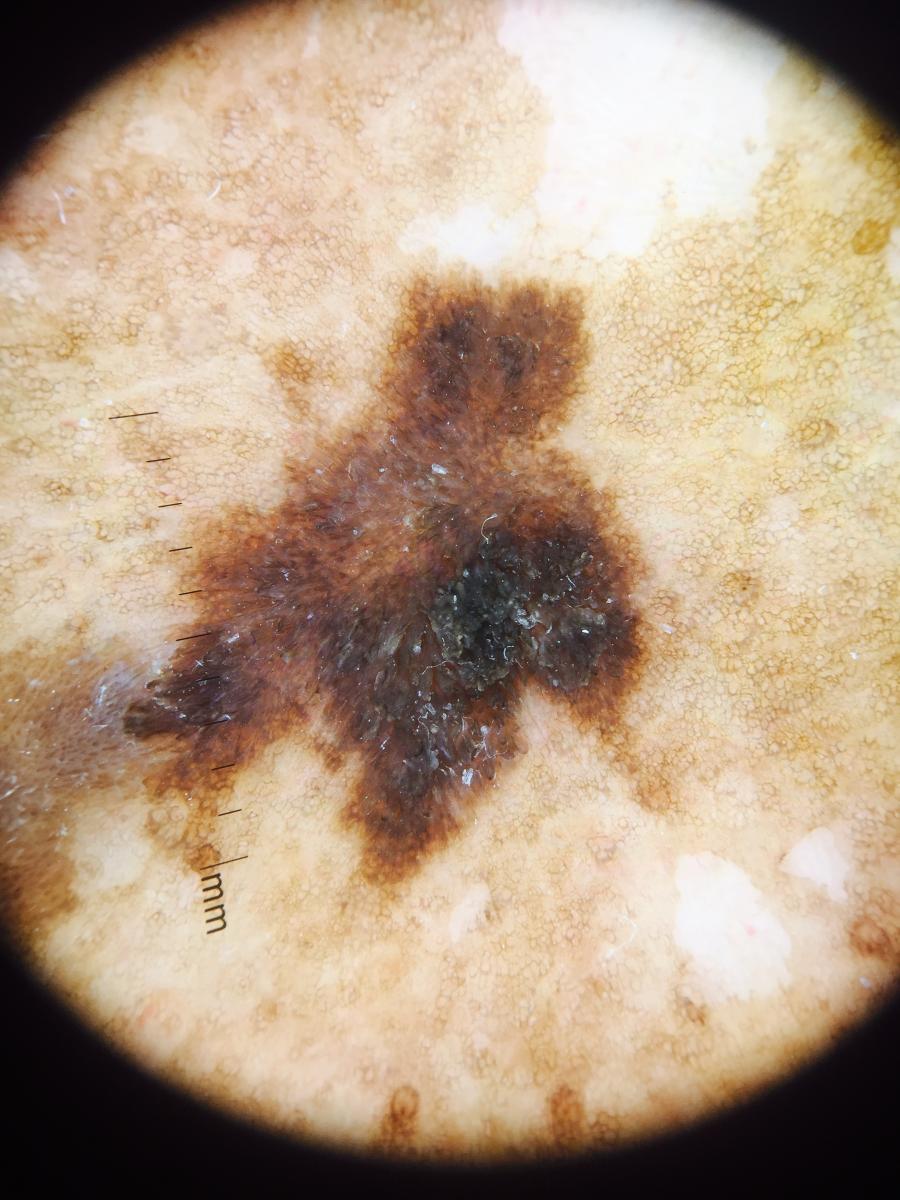

A dermoscopy examination demonstrated white collagen fibrosis without a vascular network in the areas of depigmentation. In addition, several black and brown, asymmetric hyperkeratotic plaques with irregular borders were present. A dermoscopy examination of these black plaques revealed pigmented seborrheic keratoses with characteristic moth-eaten borders but no melanoma specific structures. A dermatology consultation confirmed the diagnosis of multiple benign pigmented seborrheic keratoses.

Seborrheic keratosis previously had the term “senile keratosis.” This presents as stuck-on common hyperkeratotic plaques. They are benign cutaneous lesions with an unknown origin. They are often pigmented. Evaluating seborrheic keratosis with the A-E clinical criteria helps detects lesions that need biopsy to rule out underlying malignancy.11 It is reassuring to observe their generally uniform color and symmetry.